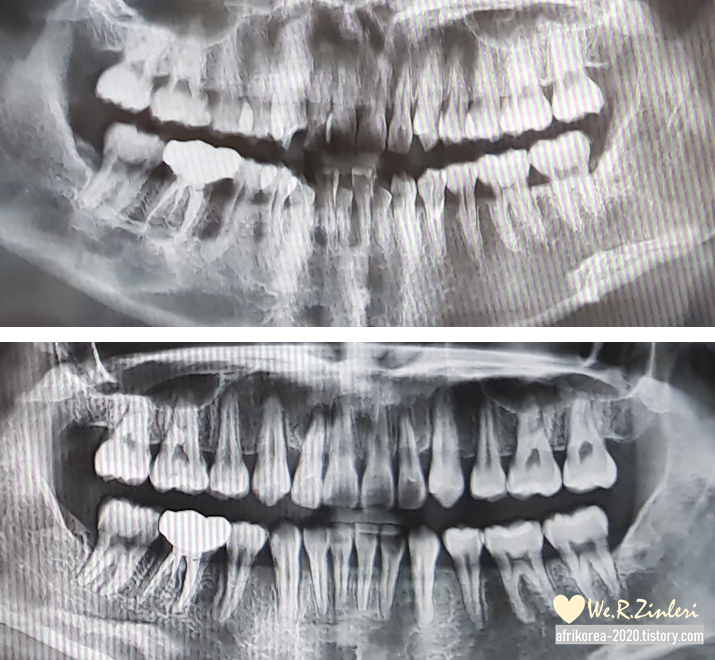

교정을 처음 시작할 때

360도 치아 엑스레이를 찍고

1년이 지난 뒤 중간 점검을 위해

한 번 더 찍게 되었다.

앞에서 지저분하게

옹기종기 모여있던 치아들은

발치 후 공간이 생겨 고르게 퍼지고 있고,

삐뚫게 나 있었던 송곳니도

가지런히 모양을 잡아가고 있다.